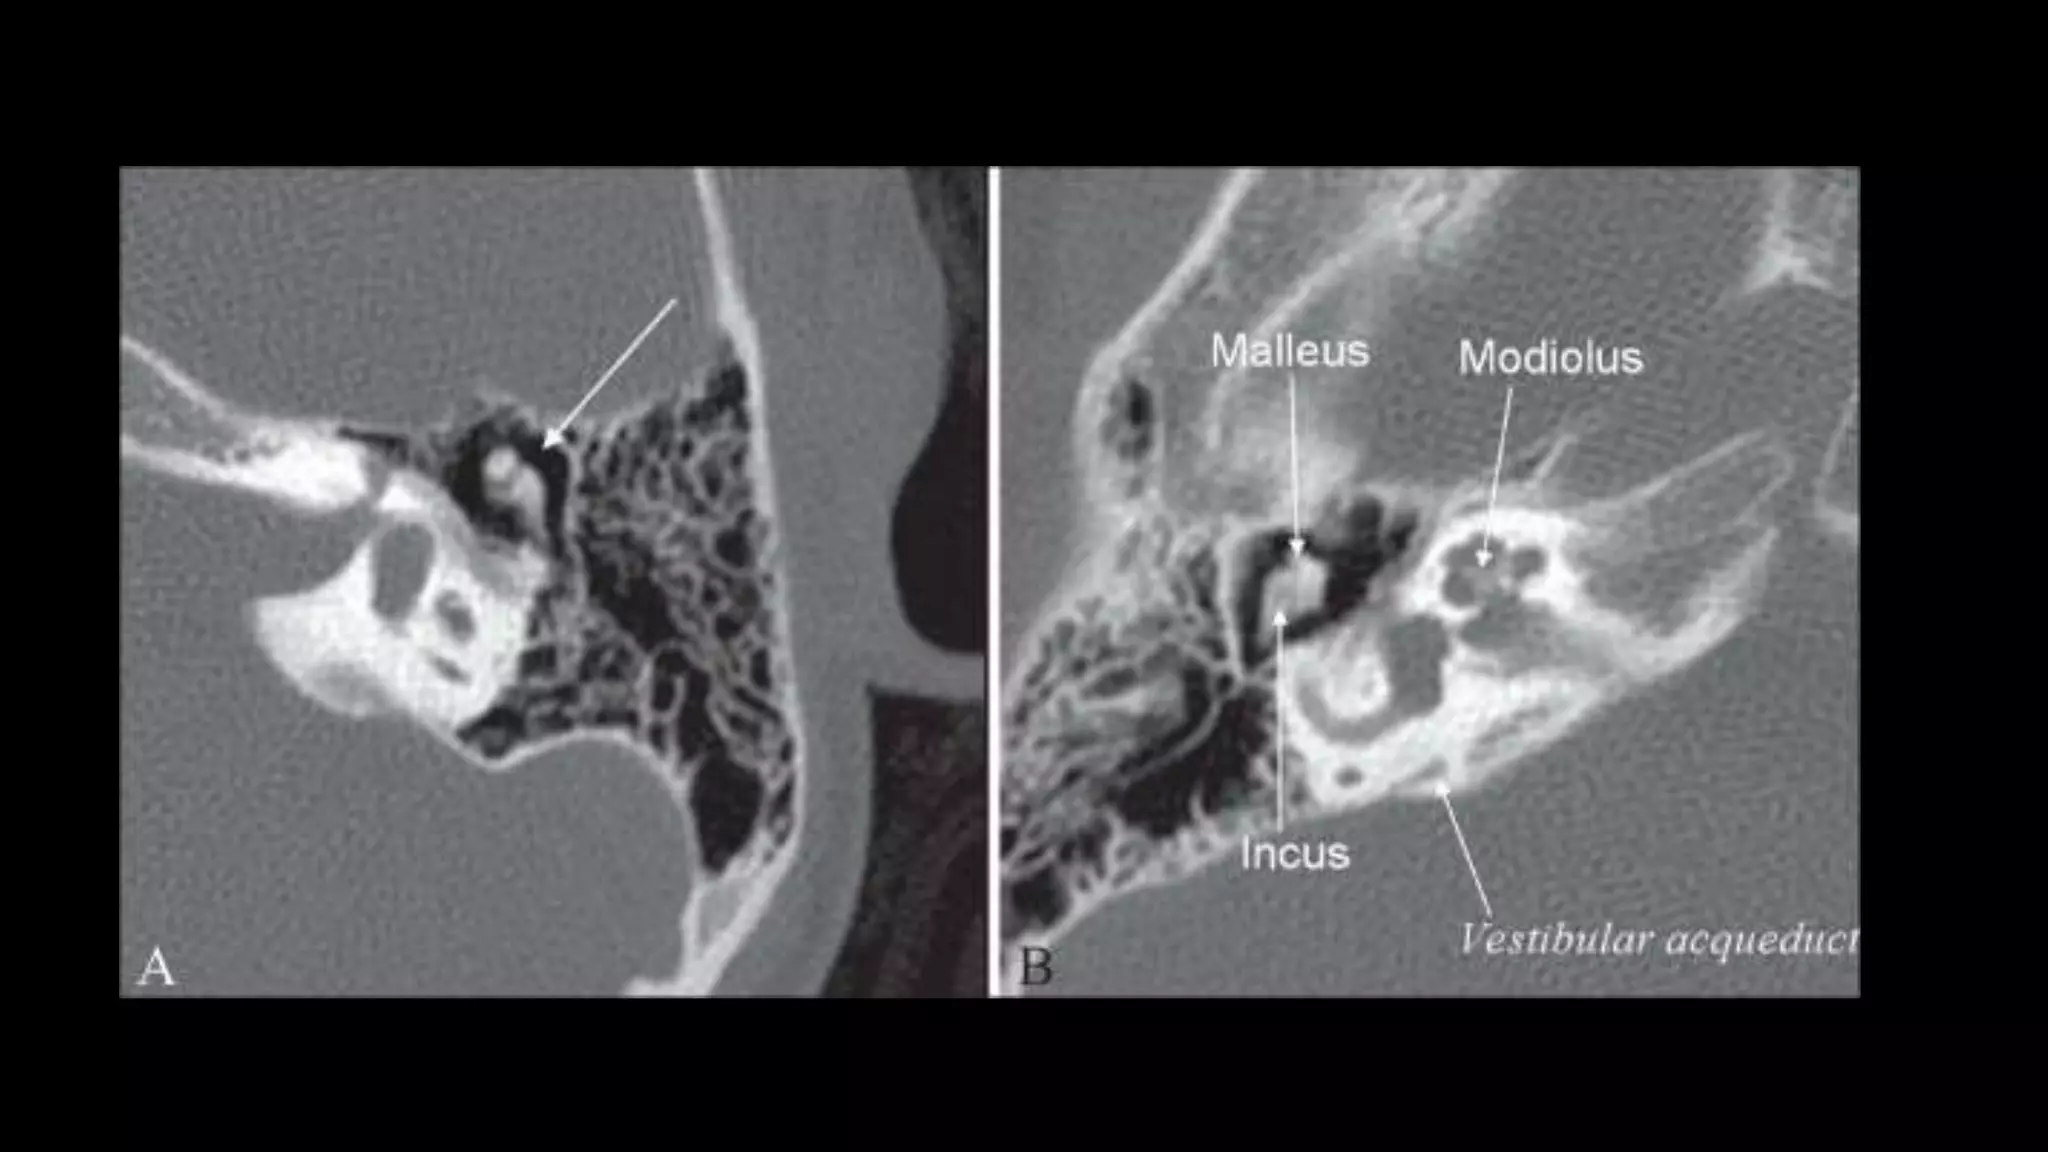

Epitympanum

It contains :

• Head of the malleus

• Malleo–incudal articulation

• Body and short process of the

incus,

• Short process of Incus projects

posteriorly towards aditus.

These structures are best

demonstrated on axial images.